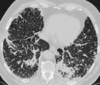

Maladie des dépôts d’immunoglobuline

non amyloïde

- Multiples kystes

- Bronchectasies monoliformes

Maladie de Birt Hogg Dubé